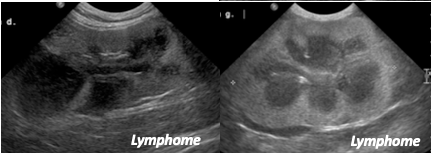

DX? (rate)

A

torsion de rate